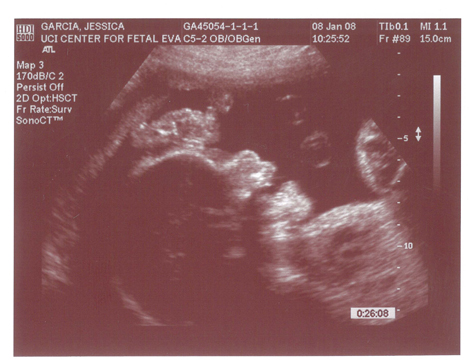

Babies First Pictures!!! ITS A BOY!

Yes we got a new dsmer coming into the world soon. We got our ultrasound today and its gonna be a boy. And shes a lot further along then we had originally thought. Shes due on April 15th which puts her at almost 6.5 months, (and really not showing it.) He weighs currently ~2lbs. He even opened his mouth while on camera which was really cool.

Here are the pics.

Pic 3: NWS Baby Penis! lol

I can't hardly even see the penis. Probably got that from his dad eh? Congrats!